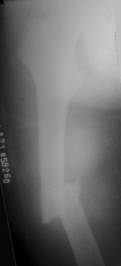

- 多项选择题2.该患者的正确诊断是: 提示: 患者 X线片如图:

A、右股骨中段骨折

B、右股骨干骨折